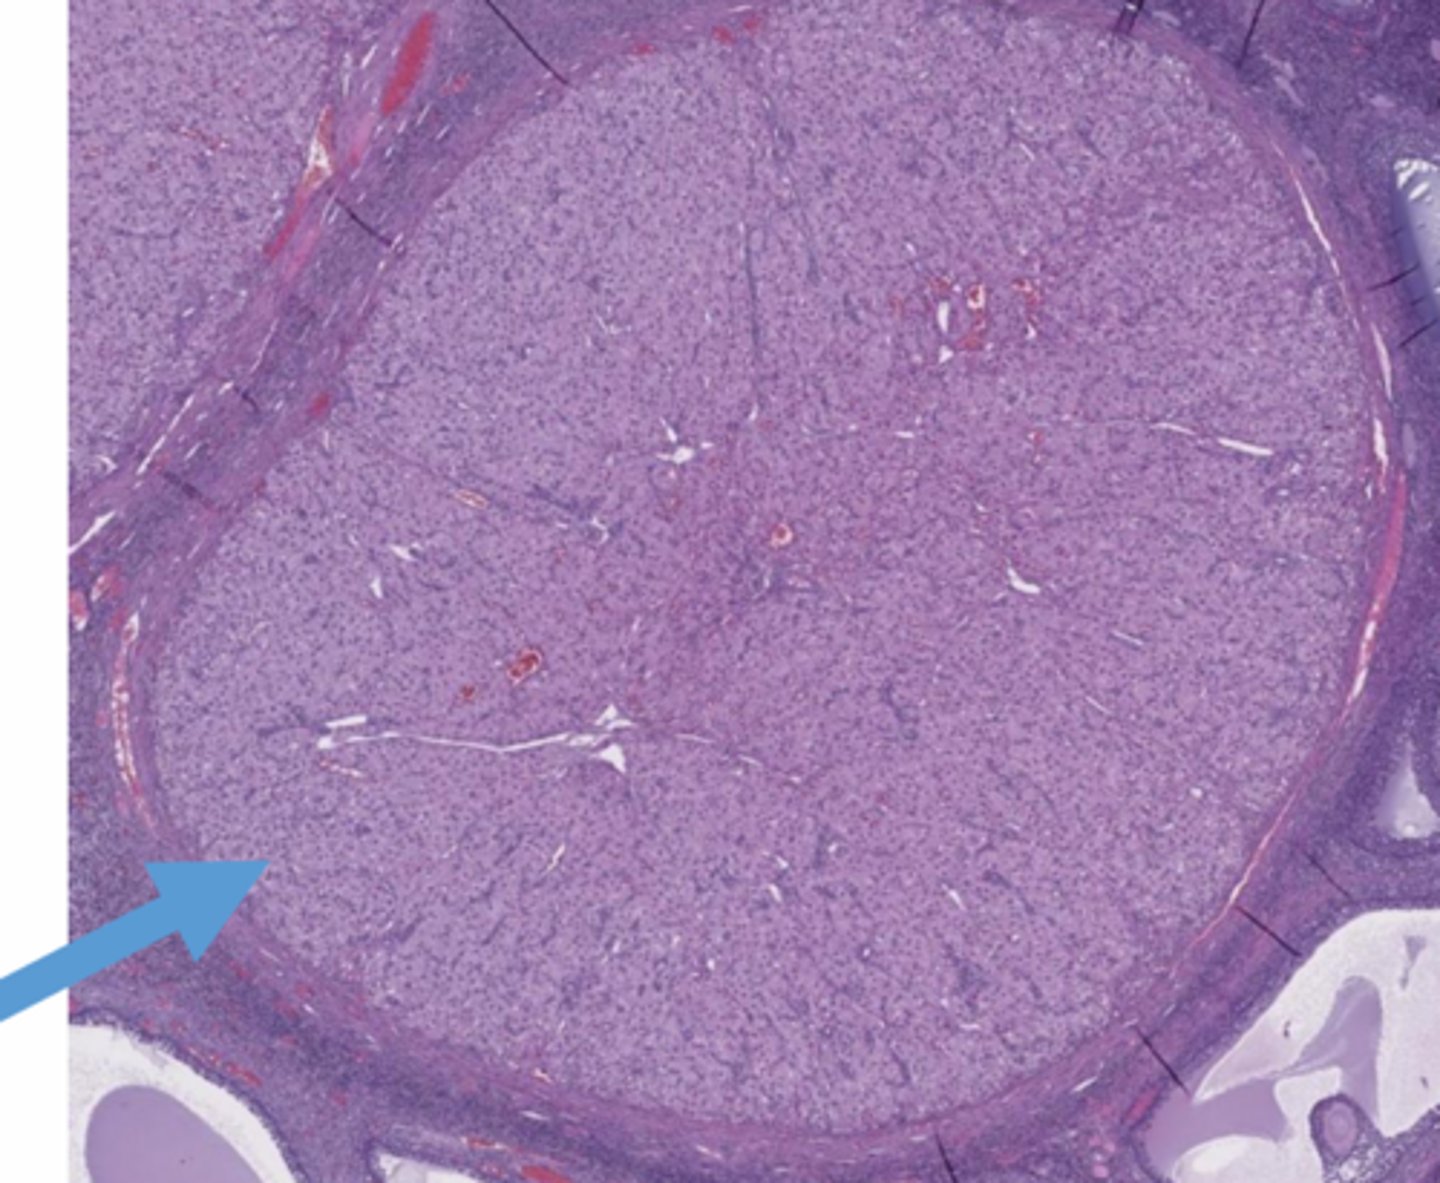

cortical stroma

red

tunica albuginea

orange

germinal epithelium

yellow

stromal

spindleoid

follicles

whats circled